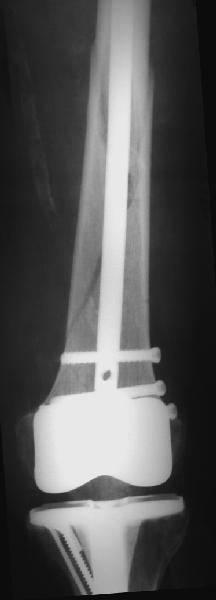

Уважаемые коллеги! 5.08.11 синтез бедренной кости пластиной LCP для дистального бедра.

Прошу совета. П-ка, 59 лет, автодорожная травма, перелом винтообразный н/3 левой бедренной кости. Планировалась закрытая репозиция и малоинвазивный доступ. по ходу операции пришлось немного открыть зону перелома для репозиции. Под контролем ЭОП вроде на столе смещение небольшое было и по оси терпимо. Сделали рентген контроль и получили вот картину. Еще обломилась головка кортикального винта. Синтез то стабильный. Только смещение не только не устранили, но кажется еще чуть больше стало (не могу) первичный снимок сделать). Склонен к ресинтезу и исправлению смещения из расширенного доступа. Как лучше выполнить репозицию? Какие можно использовать приемы репозиции? Спасибо.

конечно реостеосинтез, у Вас нижнии шуруп в линии перелома.

тип 32А1 - межфрагментарная компрессия стягивающим винтом + нейтрализующая пластина(если говорить о накостном остеосинтезе, кроме того пластинку бы подлинее этак на см 5). Ну а лучше - гвоздь с блокированием - закрыто, стабильно, с нагрузкой в послеоперационном периоде.

Коллега,для адекватной оценки перелома необходимо предоставлять предоперационные и послеоперационные снимки в двух проекциях. Насколько возможно судить по маленькой картинке прямой проекции, на первый взгляд тут простой винтообразный перелом 32-А1. В таком случае самый стабильный вариант накостного остеосинтеза - это стягивающий винт перепендикулярно линии перелома и нейтрализирующая пластина. Особых показаний к малоинвазивному мостовидному остеосинтезу нет, т.к. при нем ниже стабильность фиксации, и все микродвижения сконтрентрируются в сравнительно небольшой зоне перелома, что приведет к большим смещающим силам. Однако, если присмотрется, на снимке видно что линия перелома продолжается до начала медиального мыщелка, поэтому скорее всего это клиновидным перелом со спиральным клином 32-В1. В таких случаях возможно выполнение мостовидного синтеза, однако в данном случае дистальная часть клина не смещена относительно дистального конца бедренной кости, таким образом, мне кажется, биомеханически ситуация представляет собой среднее между А1 и чистым В1. Смещающие усилия концентрируются в проксимальной части перелома, тогда как в дистальной несмещенной части они минимальны, в т.ч. из-за интактной надкостницы. Поэтому в данном конкретном случае, при невозможности выполнения интрамедуллярного блокирующего остеосинтеза, я бы выполнил остеосинтез с двумя стягивающими винтами (с рассверливанием ближнего кортикала сверлом большего диаметра) и нейтрализирующего остеосинтеза пластиной. Причем пластина могла бы быть даже обычная.

На представленных снимках, репозиции нет, есть вальгус. Полагаю фиксация не стабильна. Перелом может и срастется, но это будет долго и без нагрузки. Если бы была использована обычная пластина, можно было бы попробовать малоинвазивно подтянуть дистальный отломок и зафиксиривовать парой винтов. Однако примененные блокирующие винты не позволят этого сделать. Как вариант, возможно открытся снизу удалить винты, сделать небольшой доступ в зоне перелома (или попробовать закрыто) ввести 1-2 винта для фиксации клина, и перепровести блокирующие дистальные винты. В любом случае, стабильность при любом из этих вариантов будет заведомо ниже чем при стягивающих винтах + нейтрализирующей пластине. Удачи.

Для принятия решения в данном случае желательно переделать прямую проекцию на длинной кассете с захватом коленного сустава - четче оценить оси, остаточные и качество фиксации; однако и имеющийся снимок не вызывает ощущения катастрофы - вполне неплохо должно срастаться.